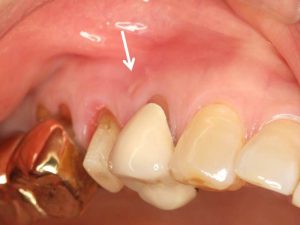

根尖病巣が原因の歯茎の腫れ。根管治療が正しくされていないために歯の中でバクテリアが繁殖し、歯槽骨を溶かして歯茎が腫れてくる。

根管治療後、ファイバーコアで支台築造を行った。根管治療を正しく行うことで根尖病巣は治癒へと向かい、歯茎の腫れも消失する。